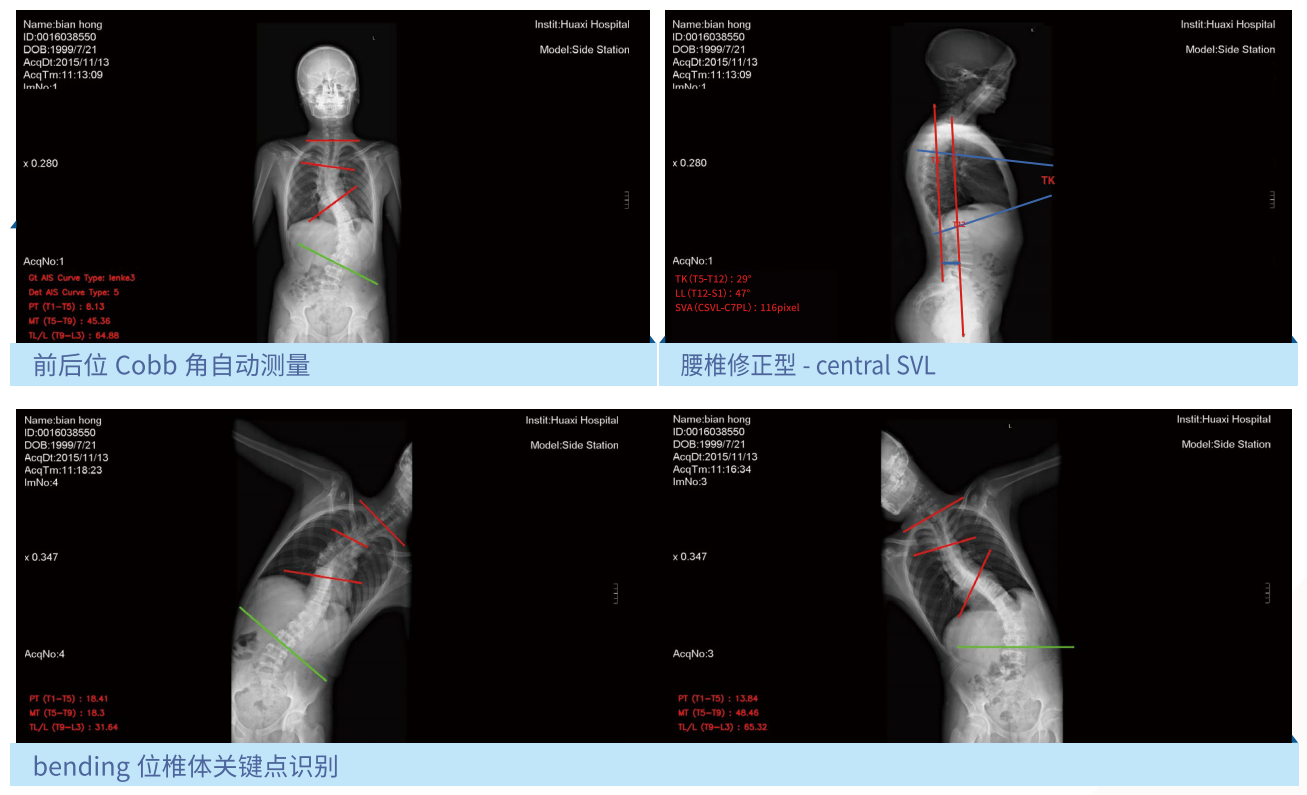

利用人工智能深度神经网络结合医学影像处理技术,智能提取背部C7、肩胛骨下角、腰窝及骶骨六个姿态关键点,智能评估冠状面Cobb角度,实现脊柱侧弯快速筛查。

1.完善的测量系统:符合临床X光脊柱全长片阅片流程的AI测量系统。

3.高稳定:大样本测试下,cobb角测量误差与医生相当(5度以内)。